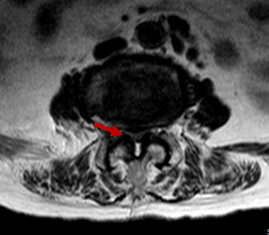

箭头所示病灶位置

然而病情并没有家属想象中简单,检查结果显示梁婆婆右侧耻骨上下支骨折、腰椎椎管狭窄,却未发现胸腰椎新鲜压缩骨折。经冯学烽主任、杨立进主治医师查体发现,婆婆还伴有臀、腿麻木症状。

冯学烽主任表示,综合检查结果和临床症状,考虑梁婆婆是摔倒后椎管压迫脊髓加重损伤,单纯治骨盆骨折无法解决行走问题,需要做传统的腰椎的开放减压内固定手术才能从根本上解决问题。